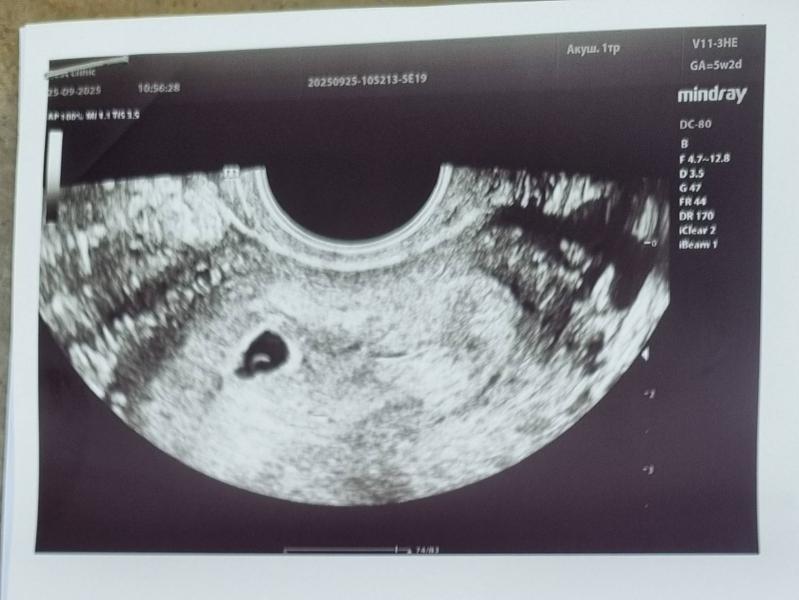

Иду на первое УЗИ (заведомо знаю ,что ещё сердечка не будет слышно), но уровень моей тревожности выше моих сил 🙈. Поэтому пошла убедиться ,что беременность маточная и всё в порядке.

Теперь как то надо вытерпеть 1,5 недельки перед ещё одним УЗИ ,что бы увидеть эмбриончик. Сейчас его не увидели...не знаю насколько это плохо или просто ещё слишком ранний срок ?!